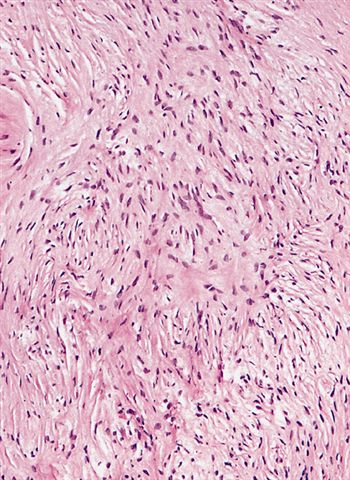

Microscopic (histologic) description

- Low to moderately cellular, bland fusiform or spindled cells with focal to diffuse whirling in heavily collagenized stroma with abrupt transition to myxoid areas

- 45% have epithelioid areas

- 40% contain poorly formed but large collagen rosettes

- Often infiltrates adjacent skeletal muscle

- Occasionally has areas of increased cellularity, atypia, necrosis or mitotic activity characteristic of intermediate to high grade sarcoma

- Recurrences may show increased cellularity and mitotic activity

Microscopic (histologic) images